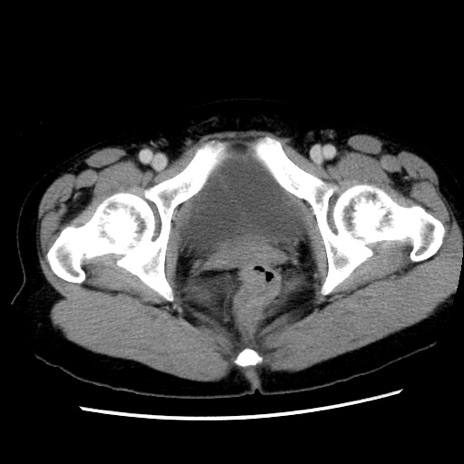

症例10(横断像)

【症例】 50歳代女性

【主訴】 腹痛

【現病歴】前日生レバーを食べた。今朝に排便あり。 昼前に突然発症の腹痛を生じ、当院救急外来を受診した。

【既往歴】 子宮筋腫にてで子宮全摘後

【身体所見】 意識清明、腹部:平坦、軟、下腹部やや左を中心に圧痛・反跳痛あり、筋性防御あり

【データ】WBC 7800、CRP 0.07